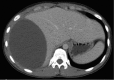

Paintball is a popular recreational sport played at both amateur and professional level. Ocular injuries are well recognised, although there is a growing body of literature documenting superficial vascular as well as deep solid organ injuries. An 18-year-old man presented with signs and symptoms consistent with acute appendicitis. Intraoperatively, a grade III liver injury was identified and packed before a relook at 48 h. No further active bleeding was identified; however, follow-up ultrasound at 3 weeks demonstrated non-resolution of a large subcapsular haematoma. The patient was readmitted for a short period of observation and discharged with repeat ultrasound scheduled for 3 months. This represents the first report of paintball-related blunt traumatic injury to the liver. Solid organ injuries of this nature have only been reported three times previously-all in the urological setting. This case also highlights issues surrounding the use of routine follow-up imaging in blunt liver trauma and provides a concise discussion of the relevant literature.